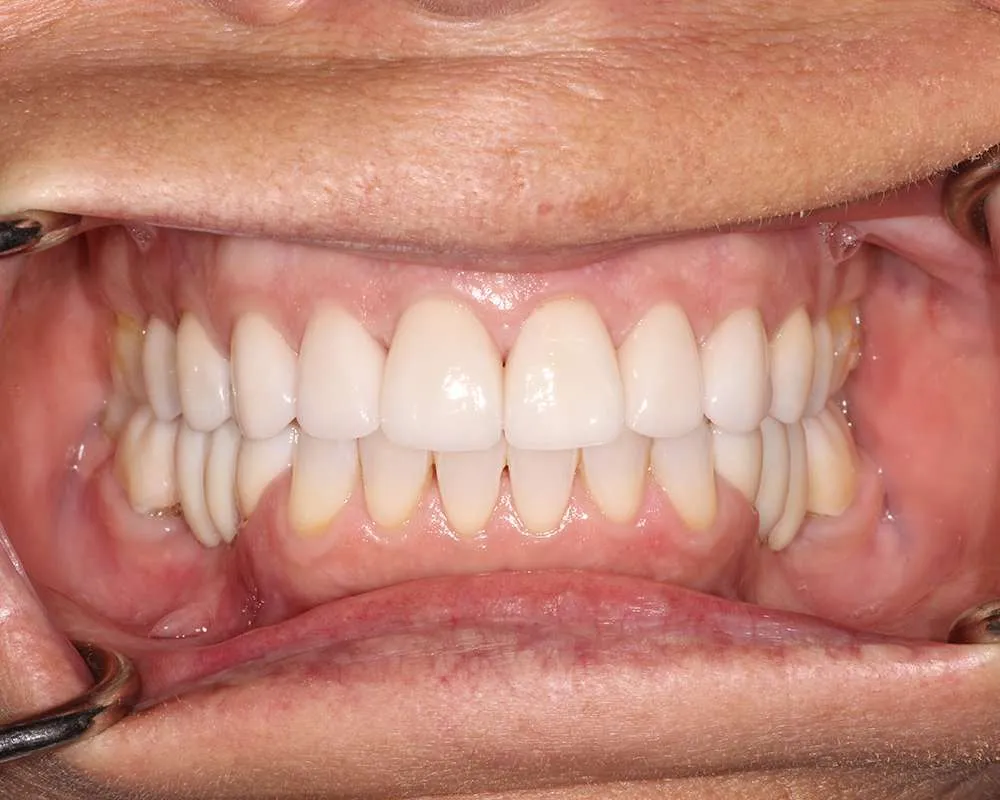

Real Stories, Real Results: Case Studies Showcasing How Our Personalized Approach Transforms Smiles and Lives

Complex Cases

Witness the Remarkable Changes We Can Achieve